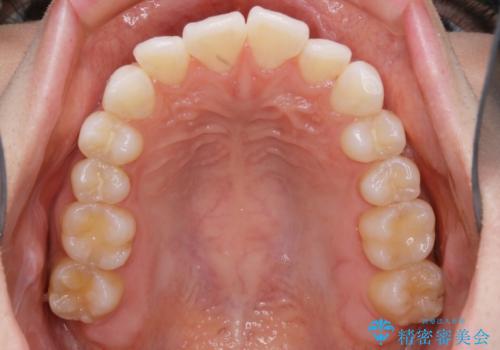

- 治療計画

- ワイヤー(片顎舌側装置)

ハーフリンガルとは上顎を裏側、下顎を表側のワイヤー装置で治療する場合をいいます。